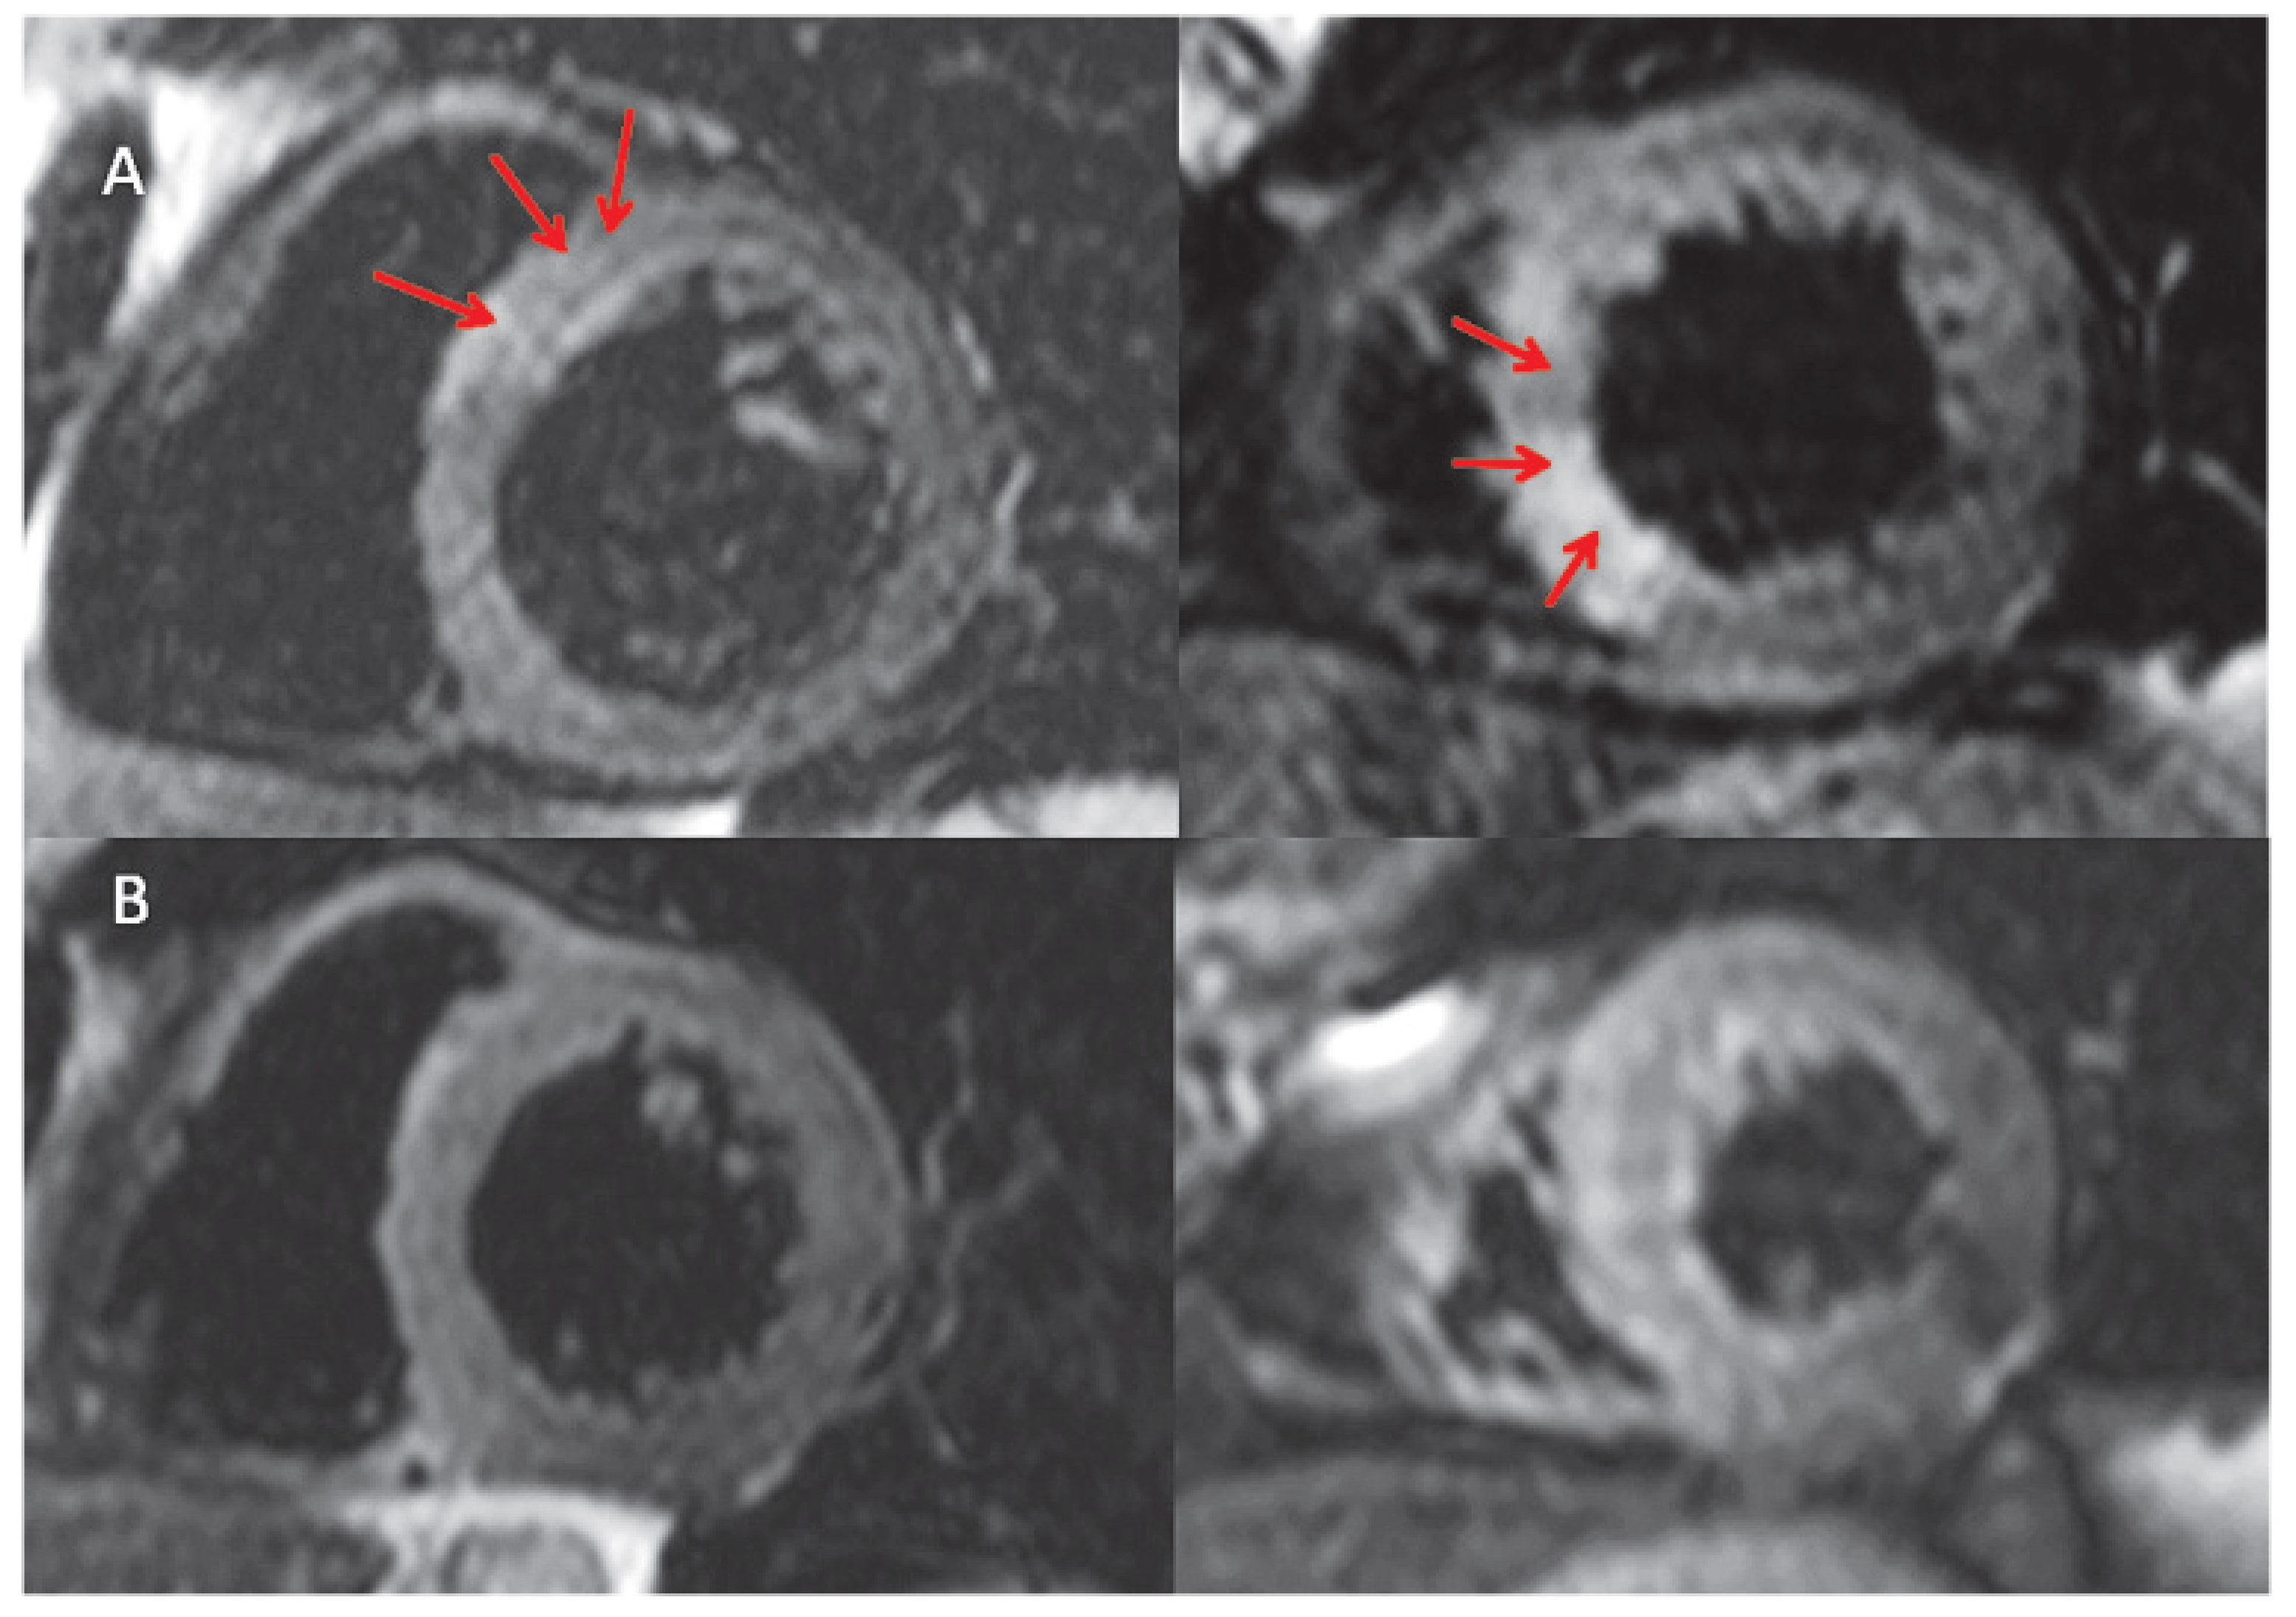

Case Report

Figure 4. A. Cardiac Magnetic Resonance (CMR) scan (Siemens 1.5T, Erlangen, Germany) 5 days after admission showing Late gadolinium enhancement (LGE) in the antero-septal and inferiorseptal wall indicating the presence of necrosis. B. Follow up CMR scan performed at 3 months. On LGE sequences there is evidence of extensive persistent, patchy, diffuse subendocardial, mid wall and epicardial fibrotic scar located in the antero-septal and inferior-septal segments.